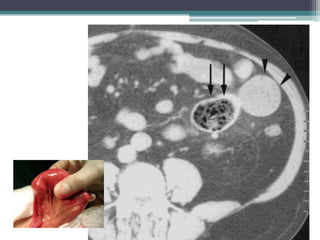

Tài liệu bàn về tắc ruột, bao gồm định nghĩa, phân loại và nguyên nhân của tình trạng này, với sự phân biệt giữa tắc cơ học và cơ năng. Các triệu chứng và chẩn đoán lâm sàng được trình bày, kèm theo phương pháp chẩn đoán cận lâm sàng như x-quang và siêu âm. Ngoài ra, tài liệu cũng đề cập đến các biến chứng và hậu quả của tắc ruột.